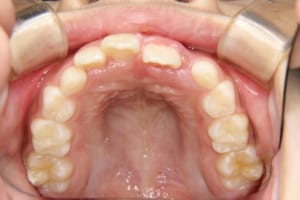

前歯のクロスバイト(部分的に前歯のかみ合わせが逆になっている)を伴う小学生の女の子の治療例

治療後

| 年齢・性別 | 8才 女性 |

|---|---|

| 主訴 | 上の歯が後ろに引っ込んでいる |

| 治療内容 | 顎の成長を利用して子供の矯正治療を行いました |

| 使用した装置 | 舌側弧線装置(リンガルアーチ) スライディングアーチ 緩徐拡大装置 |

| 治療回数 | 10回 |

| 治療期間 | 1年3か月 |

| 抜歯および非抜歯 | 非抜歯 |

| 費用(保定除く) | 405,000円(税込) |

| リスク・副作用 | 主なものとして、 ・歯の痛み ・虫歯/歯周病 ・口内炎 ・発音障害 ・食事の制限 ・歯肉の退縮(歯茎が下がる) ・知覚過敏 ・歯根吸収(歯の根が短くなる) ・金属やゴムのアレルギーの発症 ・歯髄壊死(歯の神経が死んでしまう) 等のリスクが考えられます。 |

| その他/備考 | 少ない回数、短期間で矯正治療を終えることができ、大変満足していただけました。 治療後、親御さんも矯正治療を希望され治療を開始しました。 |